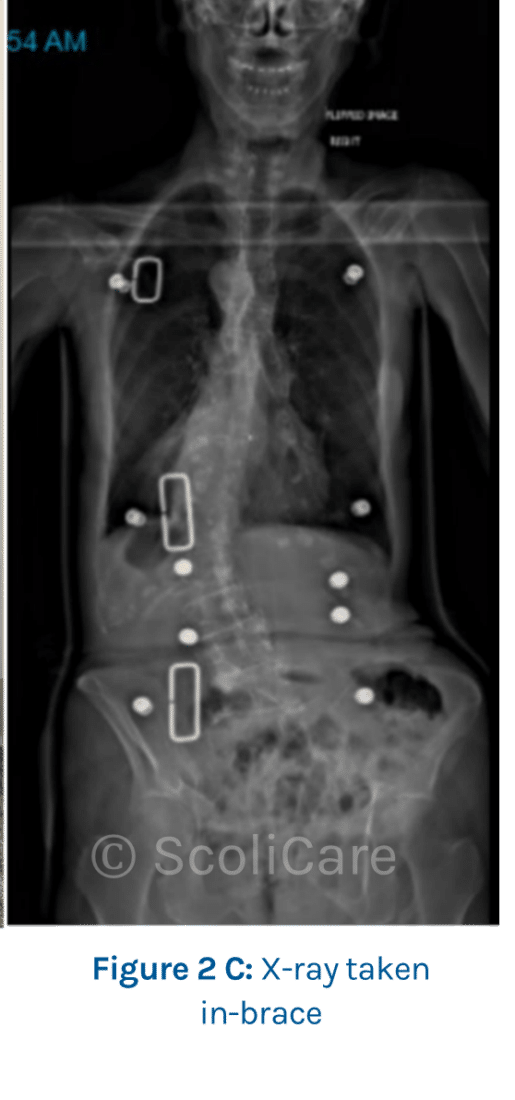

As the patient was diagnosed with a post-traumatic de novo degenerative scoliosis with unstable demonstrated progression, she was prescribed a custom-made scoliosis brace. X-ray taken in-brace shows curve improvement (Figure 2C).

The patient’s spine responded favourably to the treatment with the curve stabilized at 40° in-brace and 41° out of brace after 3 years and 4 months of part-time brace-wear (Figure 3A and 3B).